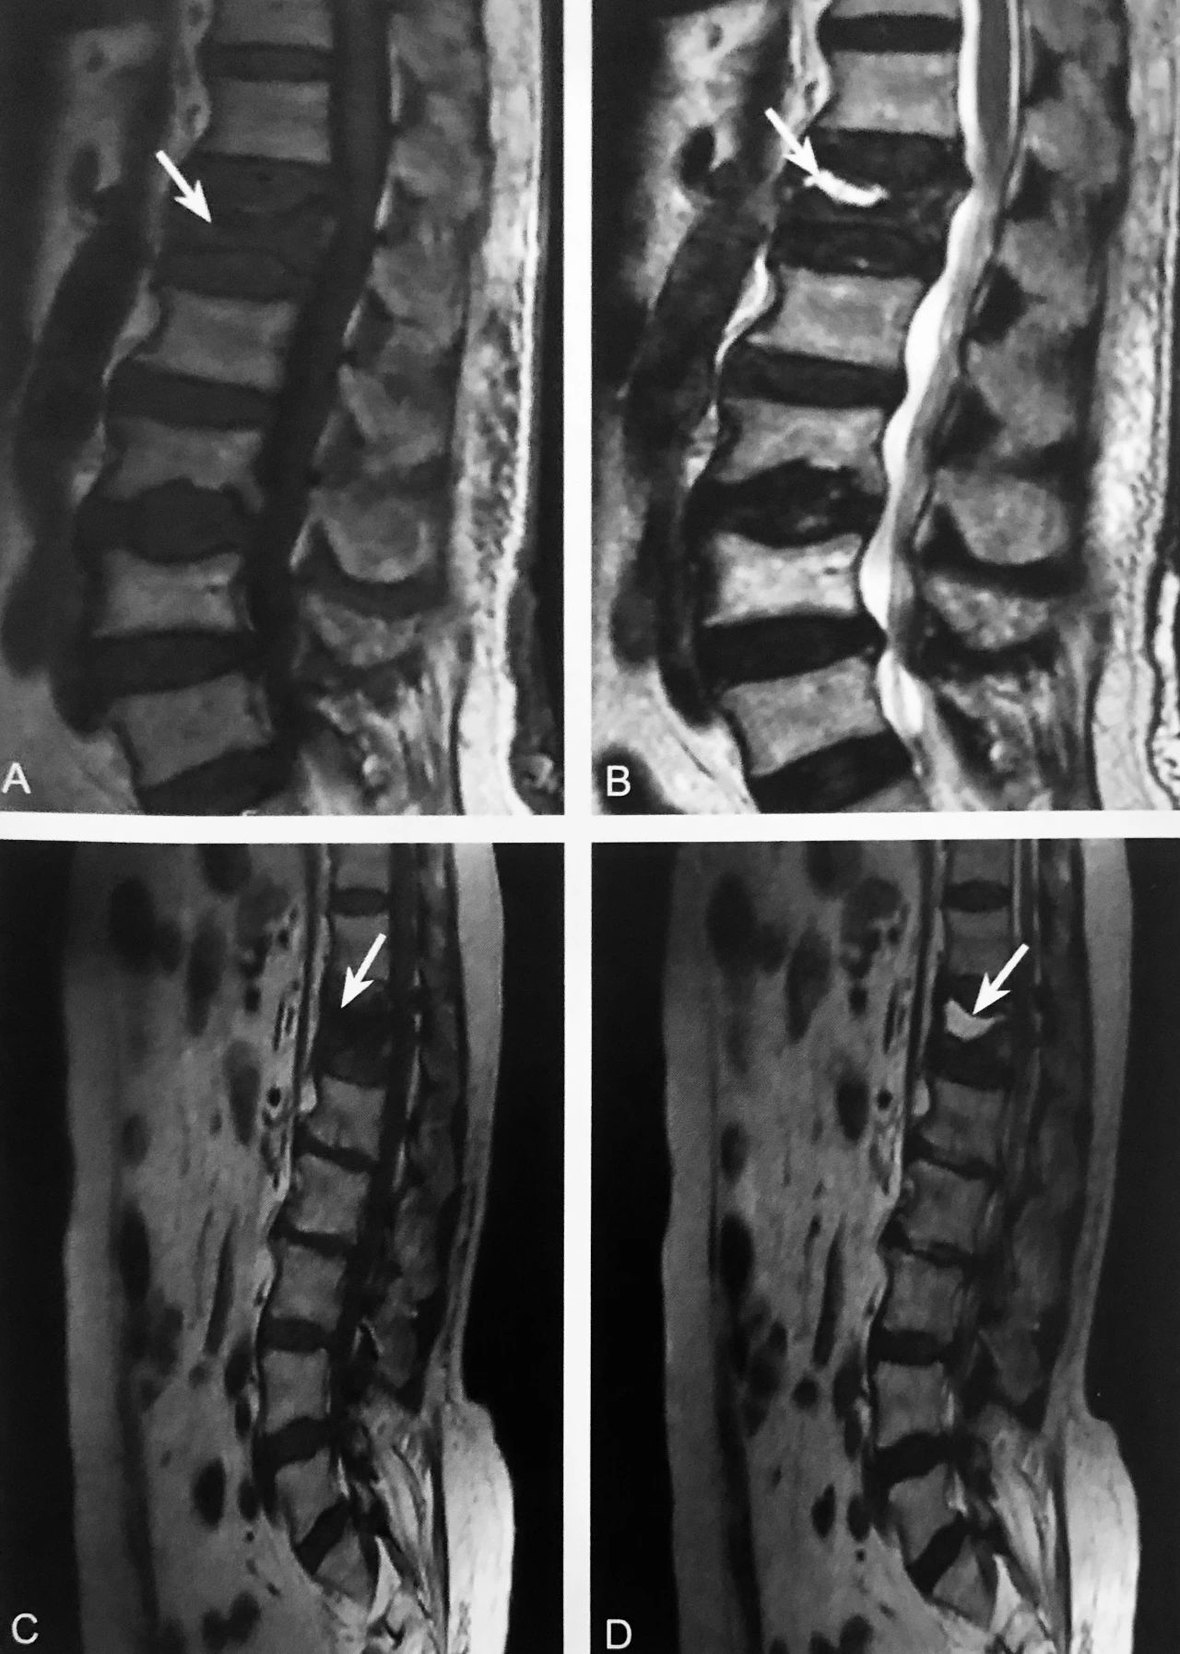

MRI 液 体 征

A~B.L1 椎体良性压缩性骨折,邻近骨髓水肿,T1WI 呈弥漫性低信号,T2WI 呈条带状高信号(箭头),位于 L1 椎体上终板下方;C~D.L1 椎体良性压缩性骨折,邻近骨髓水肿,T1WI 呈弥漫性低信号,T2WI 呈三角形高信号(箭头)

判读要点:

1、在脊柱 MRI 矢状位观察;

2、MRI 液体征常见于压缩椎体上终板下缘或下终板上缘;

3、表现为形状规则或不规则圆点状、线样或三角形,T1WI 呈低信号,T2WI 呈高信号,T2WI STIR 呈明显高信号;4、需与肿瘤侵犯推体所致压缩骨折鉴别。